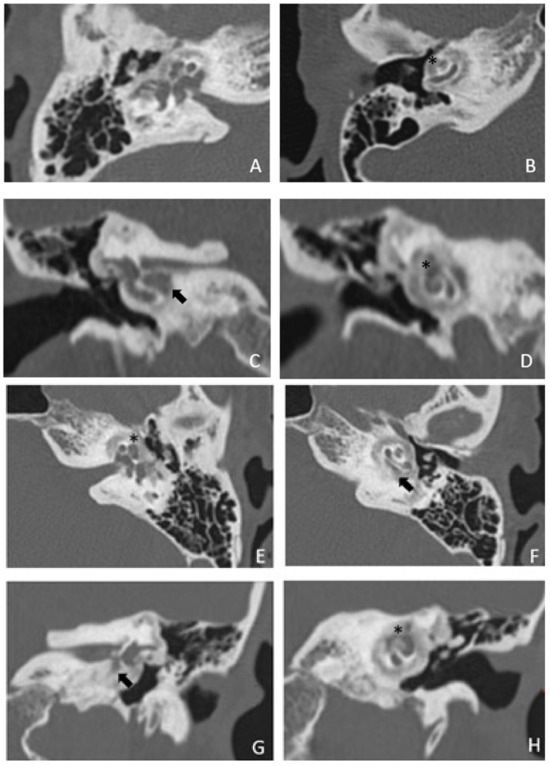

Patient #2, affected by OI-type I (COL1A1 mutation). MHL since diagnosis. Bone threshold was similar in both ears, but PTA was worse in the right ear with a larger ABG. HL progressed, but the difference between the two sides was maintained. The patient was fitted with conventional hearing aids bilaterally. Stapes surgery was not performed because of the radiological aspect (Figure 3 and Figure 4): a large cavity is present bilaterally and diffused communication between the cavity and the cochlea is evident.

Figure 3. CT images of patient #2 with osteogenesis imperfecta. (A), axial plane; (B), coronal plane. A large pericochlear cavity is visible; arrows indicate its origin from the IAC, asterisks indicate the communication of the cavities with the cochlea.

Figure 4. MR images of patient #2 with osteogenesis imperfecta. MR cisternography: (A), axial plane; (B), coronal plane. Note the fluid-signal in the newly formed cavities (white asterisk).